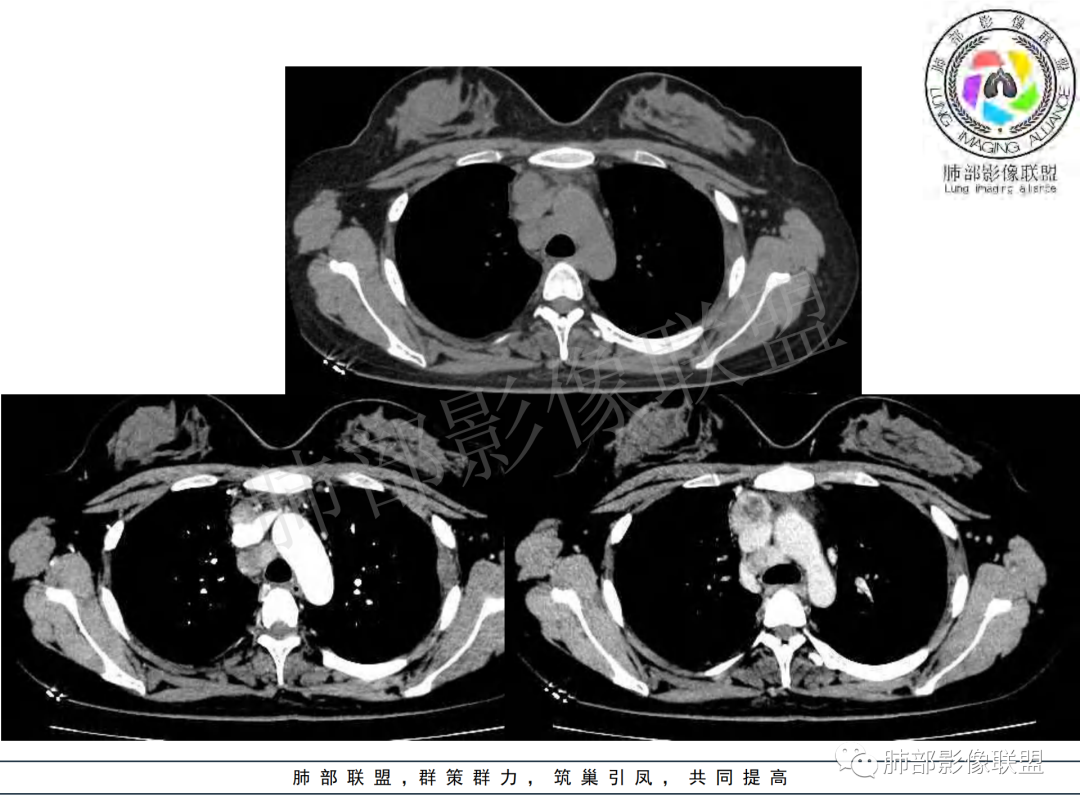

右肺肺门旁肿块,右肺中间段支气管腔内结节,增强强化不均;纵隔多发淋巴结环形强化,右侧少量胸腔积液,临床发热入院,考虑结核,鉴别肿瘤。

右肺门增大,远端花花草草不明显,支气管管壁增厚,纵隔淋巴结环形强化,年龄,病程,考虑炎性病变,结核可能,有个层面支气管截断,有强化,鉴别粘表。

纵隔多组及右侧肺门多发肿大淋巴结,部分融合,不均匀强化,内见斑片状坏死区及环状强化,后者坏死边界尚清晰,肺门区肿大淋巴结与肺组织边界不清,年轻女性,8个月病史,发热首发症状,考虑淋巴结核并向肺内侵及(破溃?),鉴别淋巴瘤

女,20,病程长达8月,发热、胸痛、右侧胸腔积液病史。胸部CT:右肺门旁不规则肿块影,右中间支气管腔内结节,纵隔多发淋巴结肿大;强化不均匀,灶性坏死灶,环形强化;右侧少量胸腔积液并局部肉芽肿样突起。年轻女性,长病程,多部位,考虑慢性炎症,结核?鉴别肿瘤。

青年,右肺门增大,见软组织肿块影,部分支气管腔结节,并管腔狭窄,增强后明显不均匀强化,伴纵隔多发肿大淋巴结,环形强化,考虑恶性,类癌,鉴别支气管内膜结核

右肺门不规则肿块,向气管腔内生长,不均匀强化,其内粘液栓,纵隔淋巴结增大,部分有坏死,胸膜结节强化,考虑恶性,粘表?类癌?鉴别结核

右肺肺门旁肿块,右肺中间段支气管腔内结节,增强强化不均;纵隔多发淋巴结环形强化,右侧少量胸腔积液,考虑结核可能,鉴别肿瘤。

年轻女性,慢性病程,发热、胸痛。右肺门旁不规则肿块影,纵隔多发淋巴结肿大;强化不均匀,环形强化;右侧少量胸腔积液;首先考虑结核,鉴别肿瘤,结节病。

女性,20岁。高热、畏寒。右肺上叶近肺门区不规则肿块,周围斑点、片小结节影伴肿大淋巴结,肿块包绕并突入右主支气管腔内,增强后肿块不均匀强化,淋巴结环形强化中心低密度,考虑结核。

本例患者,年轻女性,慢性病程,多次抗感染治疗效果不佳,实验室检查示白细胞及中性粒细胞不高,不支持普通细菌感染,虽然肺泡灌洗液X-Pert检测阴性,结合患者胸部CT结核感染亦不能排除,胸部CT主要表现为右侧肺门及纵隔淋巴结肿大,仔细观察不难发现右中间支气管内新生物凸向管腔内,增强扫描,右肺门(10R)及纵隔淋巴结(2R,4R)明显不均匀强化,内部呈不规则低密度无强化区,被周边高强化区包绕(环形强化)的特点,首先应当想到纵隔淋巴结结核诊断。淋巴结分布亦不符合肺部恶性肿瘤迁徙途径。